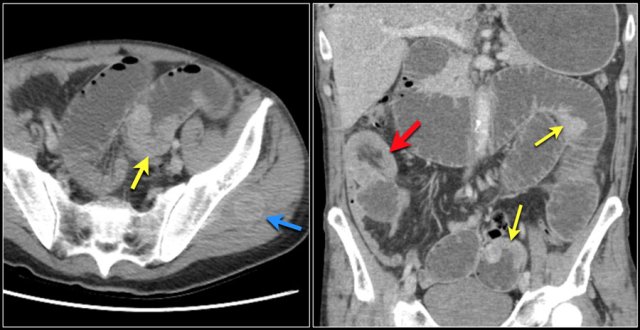

Here a patient with metastatic melanoma.

Left image shows ileal-ileal intussusception due to metastasis.

Right image shows intussusception in coronal plane as well as an enlarged mesenteric lymph node (yellow arrow) and extensive liver metastases.

Another patient with a small bowel metastasis.

This patient had a history of colon- and esophaguscarcinoma.

This patient has multiple intraluminal small bowel masses (yellow arrows), which appeared to be metastases from an unknown primary.

Also note the intussusception (red arrow) en soft tissue metastasis in the left gluteus muscle (blue arrow).